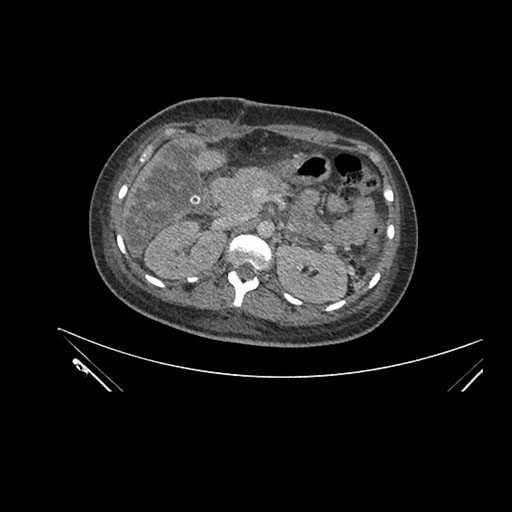

Axial Arterial

Axial Venous